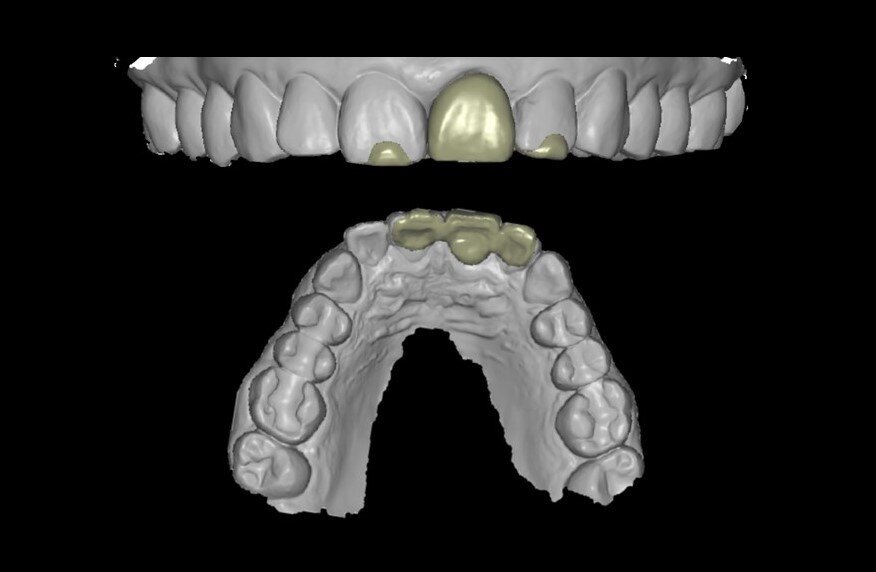

Un abutment provvisorio di Ø 4 mm con un’altezza gengivale di 2,5 mm è stato posizionato sull’impianto e non ha mostrato interferenze sulla cresta ossea, consentendo un adeguato profilo di emergenza (Fig. 19). Il guscio del dente, che è stato progettato e fresato in PMMA prima della procedura (Figg. 20, 21), è stato testato per assicurarsi che i contorni e le ali di ritenzione fossero adeguati e non causassero interferenze (Figg. 22, 23). Il lato palatale, comprendente una piccola porzione del bordo incisale, è stato aperto per consentire l’accesso al canale della vite (Figg. 24, 25). Le ali laterali del guscio del dente permettono alla corona provvisoria di rimanere immobile durante la procedura di prelievo, problema comune che i medici si trovano ad affrontare quando eseguono la tecnica pick-up immediata. Il guscio del dente è stato incollato al moncone provvisorio con composito flow fotopolimerizzabile ed è stato lasciato un sottile profilo di emergenza sulla porzione sottogengivale con lo stesso materiale (Fig. 26). A questo punto, le ali di ritenzione sono state rimosse. Senza compressione sui tessuti molli, la corona provvisoria è stata posizionata e il bordo incisale è stato ritoccato per garantire che il dente antagonista non lo toccasse nei movimenti di escursione. La corona provvisoria è stata cementata con un torque di 25 Ncm e il foro di accesso della vite è stato chiuso e lucidato correttamente (Fig. 27). Il paziente è stato visitato sette giorni dopo per il controllo radiografico postoperatorio e periapicale (Figg. 28, 29).

Fig. 20_Corona provvisoria realizzata con coDiagnostiX (Dental Wings).

Fig. 21_Corona provvisoria fresata in PMMA.